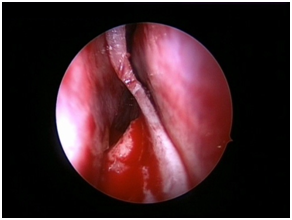

Nasal Endoscopy is done to assess the septal deviation and spurs (Figure 1) ( Figure 2). Septal infiltration is carried out with a solution of 2% Xylocaine with 1: 100,000 adrenaline in the sub-mucosal plane. It is given with a single prick at the inferior most part of the nasal septum at the junction of the septum with the floor of the nasal cavity anterior to the mucocutaneous junction. The infiltration is given at the same point on both the sides (Figure 3). The incision is always given on the deviated side. It is given anterior to the mucocutaneous junction because the skin present at that place is thick and chance of a tear of the flap is less (Figure 4). The mucoperichondrial flap is raised on the deviated side with a Freer’s elevator strictly under vision. The flap is not to be raised beyond the deviated part because the part of the septum posterior to the deviation is not under direct vision (Figure 5) (Figure 6). The caudal end of the septum is then palpated and an incision is given on the cartilage 1cm behind the columella. This 1cm of the cartilage is saved to prevent post operative tip deformities (Figure 7). The cartilage is sliced and the opposite side is entered, the mucoperichondrial flap of the opposite side is then elevated with a Freer’s elevator. A cut is given in the septal cartilage as high as possible. A septal window is created and a Ballenger’s swivel knife is taken and lodged in the place where the cartilage was cut. Creation of a septal window thus increases the area of exposure (Figure 8) (Figure 9). The flap on the non-deviated side is elevated till the bony-cartilaginous junction.

After reaching the bony-cartilaginous junction, the flap is elevated downwards towards the floor. The elevation is done from posterior to anterior direction. This makes the flap on the non-deviated side safe. The Freer’s elevator is placed in the bony-cartilaginous junction and the inferior strip of cartilage is sliced off from the maxillary crest from posterior to anterior direction. The strip of cartilage is gently swung out. In case of any spur, bony or cartilaginous, the flap over the spur is never elevated directly. The cartilage/bone above the spur is cut at multiple levels and the pieces are removed with the help of a Blakesley’s forceps. The Freer’s elevator is placed between the spur and the flap and the spur is gently pushed to the non-deviated side and is removed with the Blakesley’s forceps (Figure 10). In case of any deviation or spur from the maxillary crest, it is chiseled out. The direction of the chisel is always towards the maxillary crest only. The flaps are repositioned and a diagnostic nasal endoscopy is done to assess the patency of the nasal cavities. Nasal packing is done using commercially available sponge packs made from cross-linked polyvinyl alcohol (Merocel®) using a Thudicum’s nasal speculum, in order to prevent the reflection of the flap at the incision site. The immediate post-operative management includes intravenous antibiotics and analgesics. Nasal pack is removed on the second day after surgery and patients are advised oral antibiotics, analgesics, anti-histaminics and decongestant nasal drops for one week. Patient is advised saline nasal douching for a week and discharged on the second day after surgery with a prescription of oral antibiotics, anti-histaminics and decongestant nasal drops for one week. Saline nasal drops are given for two weeks after surgery.

Figure 10 Removal of the spur.